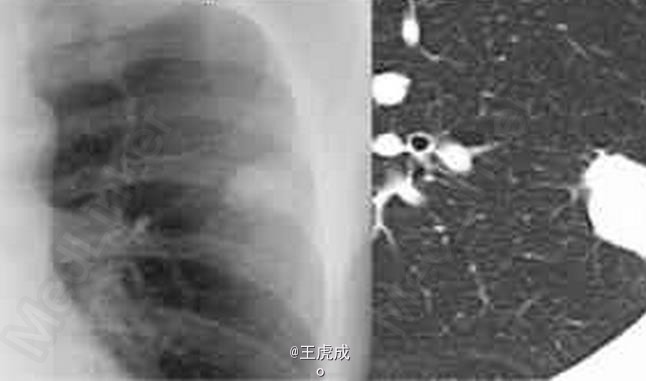

男,50岁,因查体发现肺部结节影6月余前来就诊

患者无明显症状 辅查X线,左肺上叶结节影,CT左肺上叶结节,病理:结核瘤

肺结核瘤 处理:积极对症治疗,抗结核处理

肺结核球是肺结核纤维化包裹,一般无传染性,但有可能会复发再感染